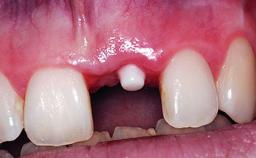

Replacement of a Compromised Upper Right Central Incisor: Hard- and Soft-tissue Augmentation, Late Placement of an RC Bone Level Implant

A 36-year-old male patient with a compromised maxillary central incisor was referred by his general dentist for consultation. The patient’s chief complaints were the gradual debonding of a temporary crown on the right central incisor and unsatisfactory esthetics due to an increasing diastema between the right central and lateral incisors. The patient reported a traumatic event some years previously, when a crown had been placed after root-canal treatment. The referring dentist wanted to provide a new crown restoration, but was concerned about the condition of the residual root. Anamnesis was negative for any other dental or periodontal pathology in the remaining dentition. The patient reported taking no medications: He was a smoker (10 to 15 cigs/day) and had realistic esthetic expectations.

Bone Augmentation Horizontal|Simultaneous|Staged

Soft Tissue Grafting Simultaneous